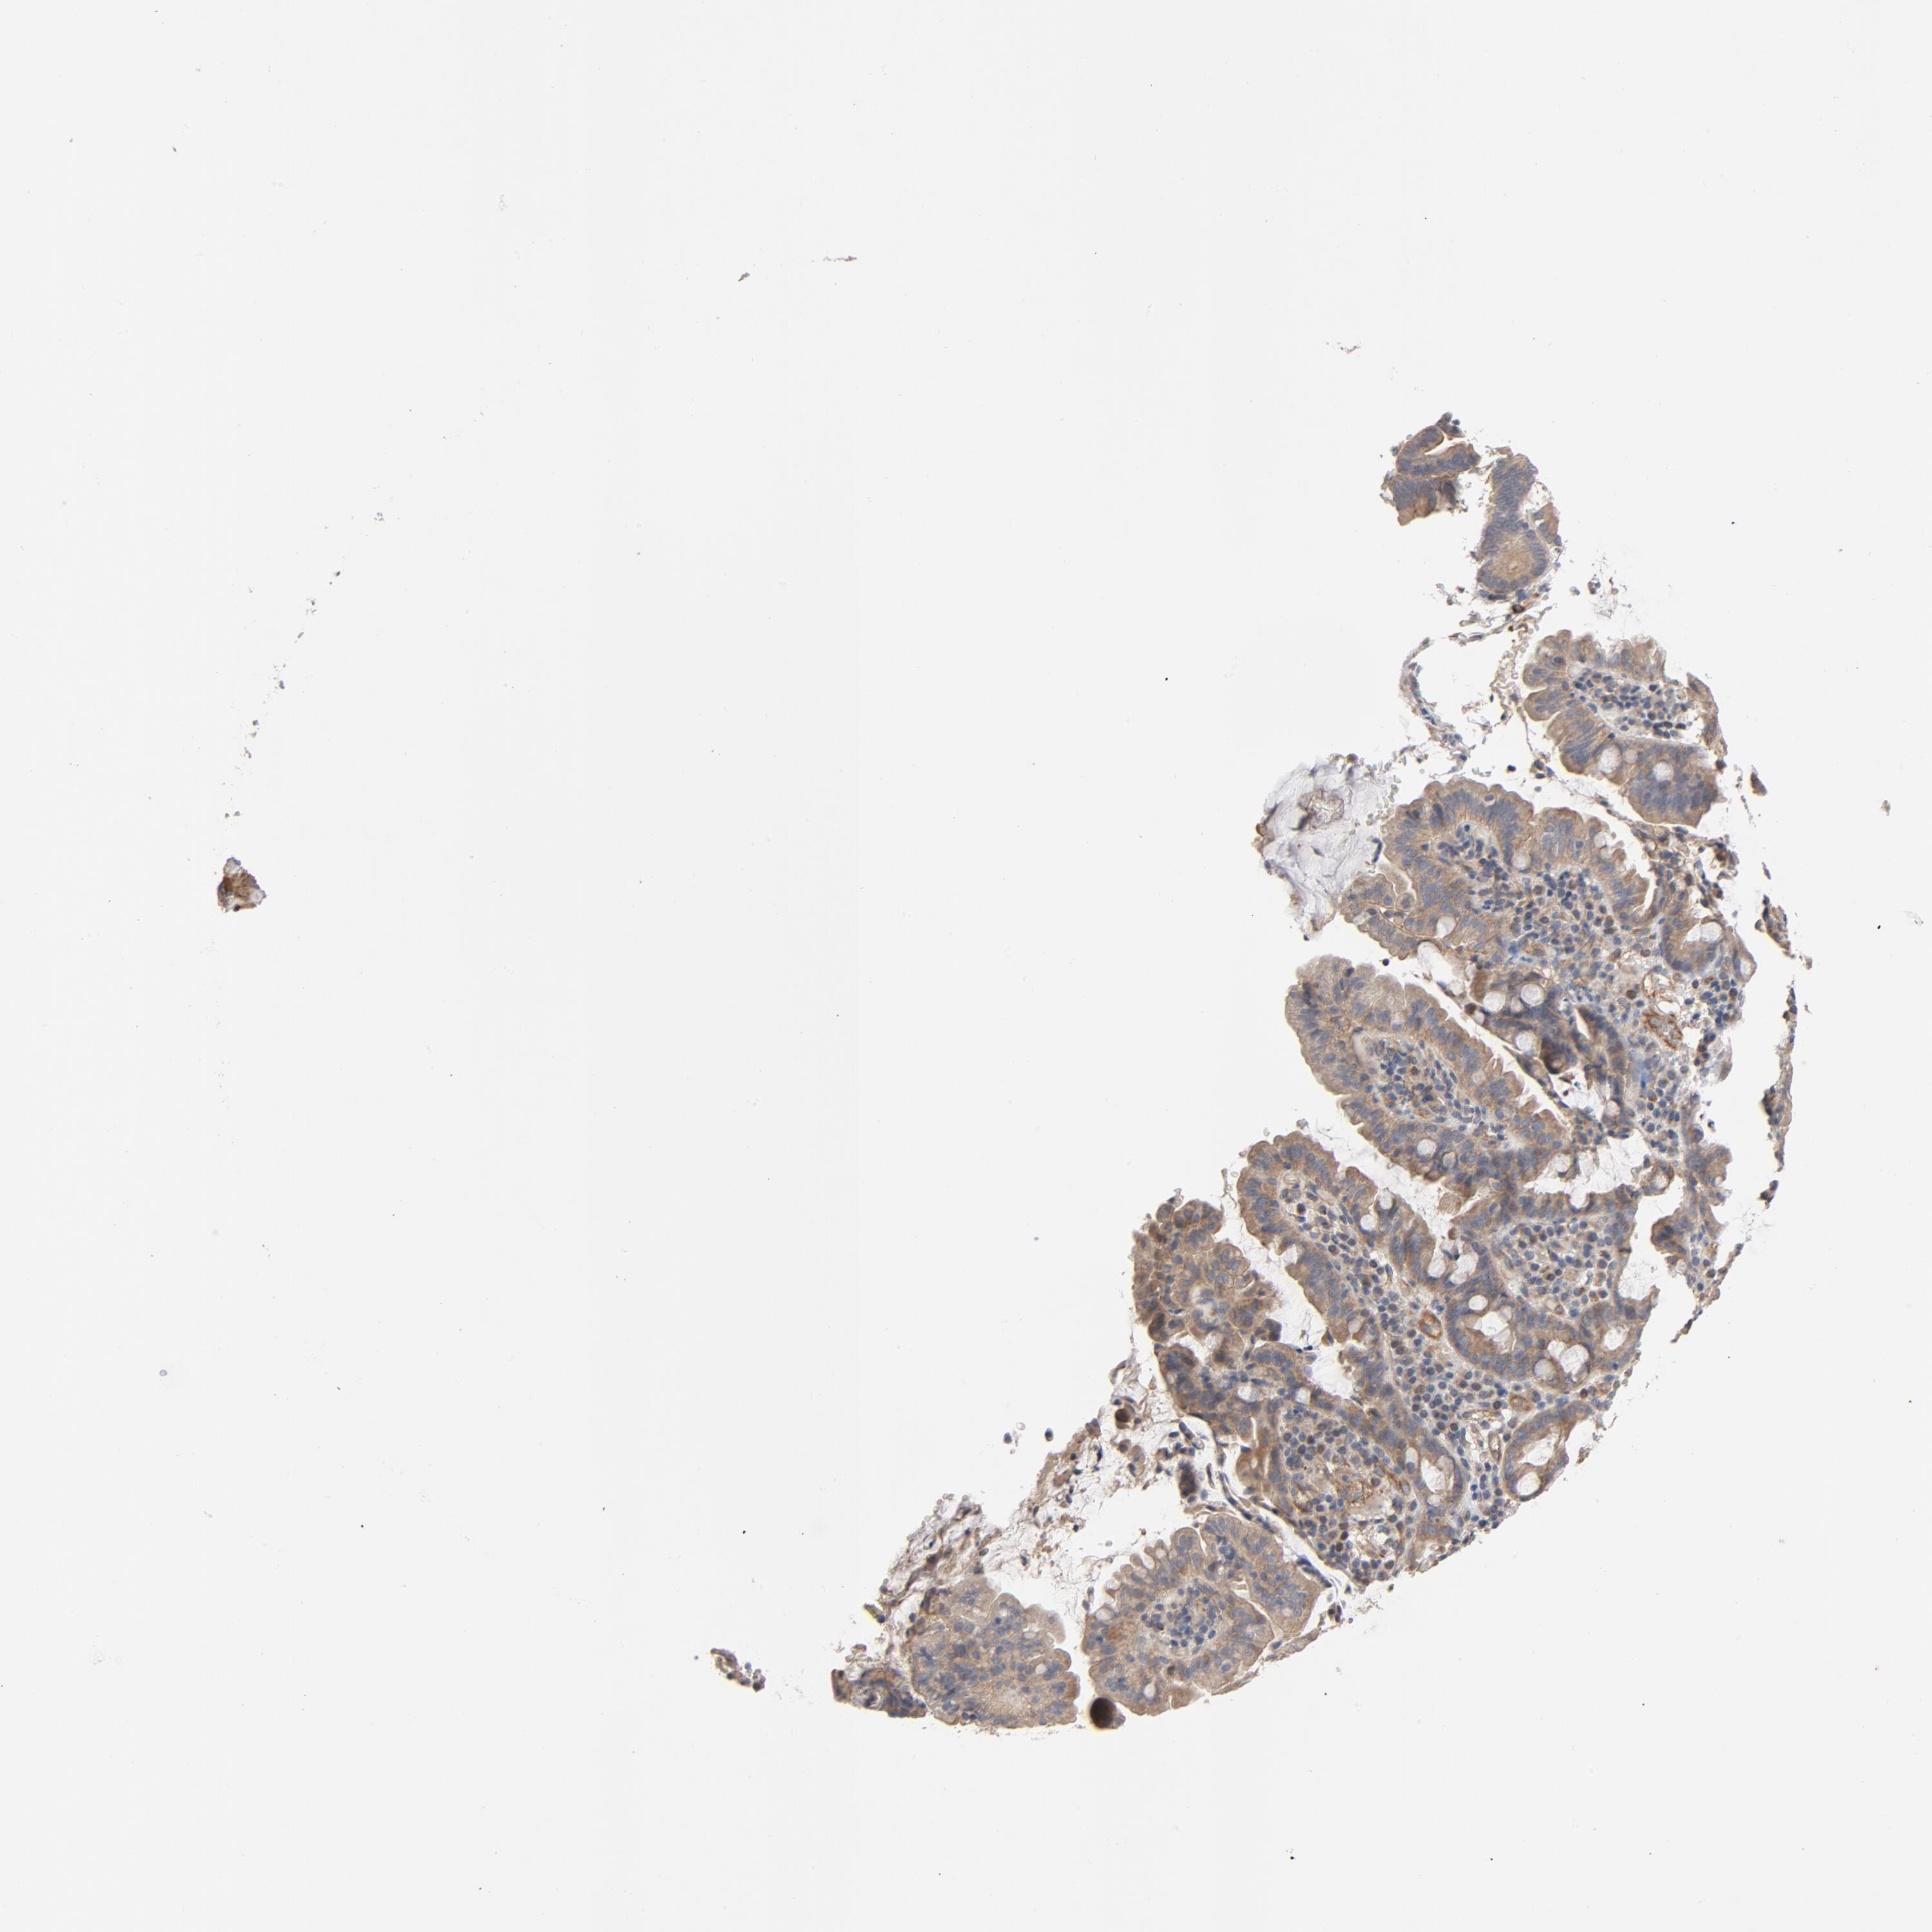

PANCREATIC CANCER - Protein expressioni

A mouse-over function shows sample information and annotation data. Click on an image to view it in a full screen mode. Samples can be filtered based on level of antibody staining by selecting one or several of the following categories: high, medium, low and not detected. The assay and annotation is described here.

Note that samples used for immunohistochemistry by the Human Protein Atlas do not correspond to samples in the TCGA dataset.

Antibody stainingi

Antibody staining in the annotated cell types in the current human tissue is reported as not detected, low, medium, or high, based on conventional immunohistochemistry profiling in selected tissues. This score is based on the combination of the staining intensity and fraction of stained cells.

Each image is clickable and will lead to virtual microscopy that enables deeper exploration of all samples and also displays staining intensity scores, fraction scores and subcellular localization as well as patient and tissue information for each sample.

Antibody HPA003747

Antibody HPA019769

Adenocarcinoma, NOS

Adenocarcinoma, metastatic, NOS